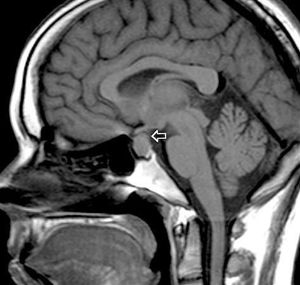

Note the tumor mass of pituitary gland revealed by this MRI.Prolactinoma symptoms result from hypersecretion of prolactin and its inhibitory effects, prolactin cells (aka lactotrophs or mammotrophs) are located in anterior pituitary. Symptoms of Prolactinoma in women are amenorrhea, galactorrhea, and infertility. In men the symptoms are low libido and headache. Because of the compression of optic chiasm there will be visual field loss in bitemporal hemianopsia. Treatment of this tumor is by dopamine agonists (bromocriptine or cabergoline) as they supress the secretion of prolactin.